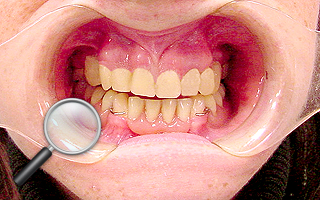

2. Pacjent z licznymi wypełnieniami (plombami), zgryzem głebokim, zaburzona estetyka

i funkcja układu narządu żucia (diastema).

| 2a. Pacjentka przed leczeniem |

2b. Gotowe mosty pełnoceramiczne

na podbudowie cyrkonowej |